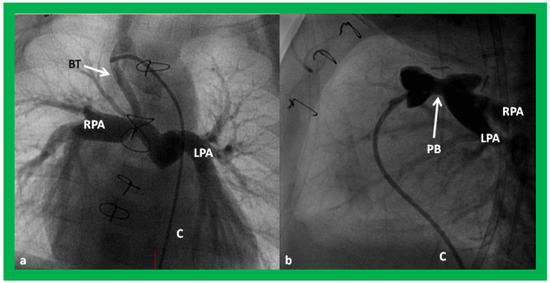

Angiographic counter parts of both the palliative procedures are shown in Figure 24, to have better comprehension of the anatomy of these procedures.

Figure 24. Selected cine frames in postero–anterior (a) and lateral (b) views, demonstrating a Blalock–Taussig (BT) shunt (arrow in a) to care for infants with decreased pulmonary blood flow (a) and pulmonary artery banding (PB) (arrow in (b)) in babies with increased pulmonary blood flow (b), respectively, during Stage I of Fontan procedure. C, catheter; LPA, left pulmonary artery; RPA, right pulmonary artery. Neonates with adequate pulmonary blood flow do not need any intervention and can go directly to Stage II at about the age of 3 months. Reproduced from Rao PS, Indian J Pediatr 2015;82:1147–1156 [36].

Applsci 11 09472 g024